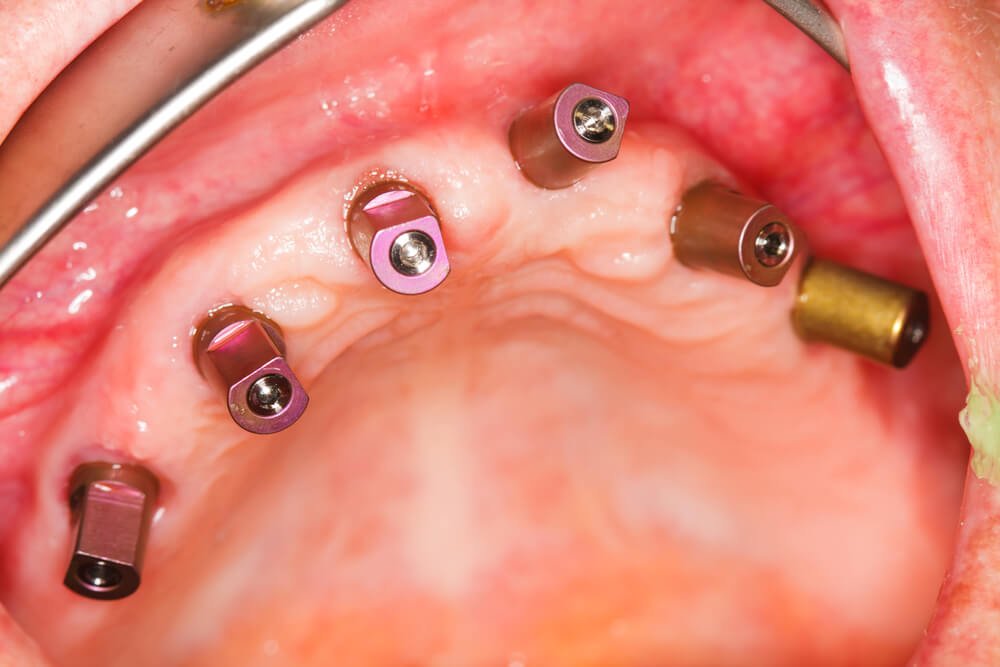

הסוג הנפוץ ביותר של שתלים דנטליים הוא שתלים בצורת שורשים, ובעקרון זה אומר שהם שורשים חליפיים של שיניים המשמשים להחלפה של שורשי השיניים הטבעיות באזורים בפה שבהם חסרות שיניים. שתלים דנטליים אלה עשויים מתרכובות טיטניום המתאימות לשימוש כירורגי. אין שום אלרגיות ידועות למתכת זו והוכח שהיא בטוחה מאוד בתור חומר השתלה. הסיבה שכל כך חשוב להחליף את שורש השן כמו גם את החלק הגלוי של השן (הכתר) היא ששורשי השיניים הטבעיים משמרים את העצם.

- שלב 1 – בקפידה רבה השתלים מוחדרים אל עצם הלסת. לאחר מכן רקמות החניכיים נסגרות ושלב ההחלמה מתחיל. זה עשוי להימשך 6-3 חודשים. לעתים, ניתן להתחיל להשתמש בשתלים מיד.

- שלב 2 – יצירה וקביעה של השן או השיניים החדשות למסגרת השתלים. השתלים יכולים להחליף שן יחידה, מספר שיניים או את השיניים התותבות שלך.